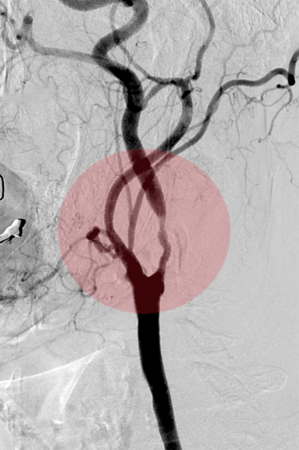

Behandlung der eingeengten Halsschlagader:

Patienten mit hochgradigen arteriosklerotischen Einengungen der Halsschlagader mit oder ohne Symptome eines Schlaganfalles, können neben der operativen Behandlung auch interventionell behandelt werden. Dazu wird ein Stent in die eingeengte Arterie eingesetzt. Ein spezielles Filtersystem verhindert dabei das Verschleppen von Wandablagerungen in die Hirnarterien und damit die Gefahr einer während der Behandlung auftretenden Durchblutungsstörung des Gehirnes.